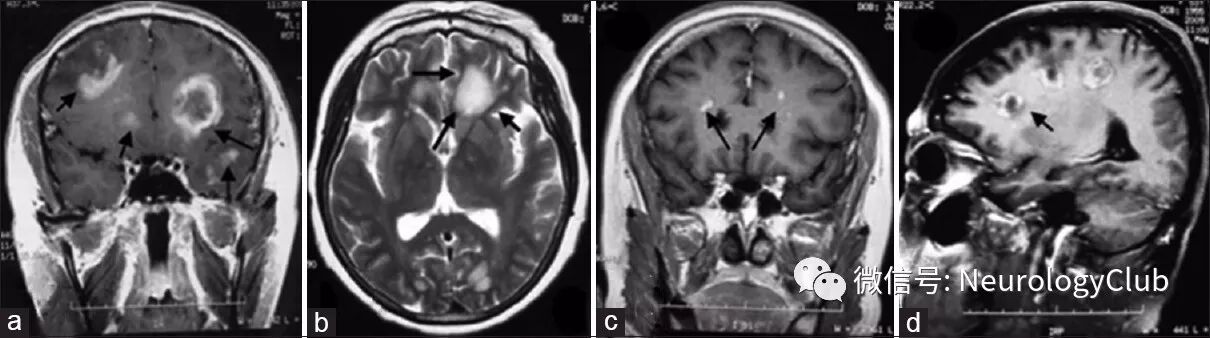

需与星形胶质细胞瘤,PCNSL,原发性中枢神经系统血管炎(PACNS)以及其他(如生殖细胞瘤,脑转移瘤等)鉴别(可参见文末相关链接)。

图8:一例III级间变性星形胶质细胞瘤患者,T2WI可见胼胝体压部,双侧颞叶弥漫高信号病灶(a);一例PCNSL(弥漫大B细胞淋巴瘤)患者,可见左侧基底节区大的圆形强化肿块伴上部“脐凹”(b);另一例PCNSL(弥漫大B细胞淋巴瘤)患者,可见多发脑室旁和脑室内病灶,均匀强化伴“雨滴”征或“尖角”征(c);一例II级弥漫性星形胶质细胞瘤患者,T2WI可见脑桥弥漫高信号伴脑干明显水肿,病灶将基底动脉前部分包绕其中(d)

图9:一例病理确诊的PACNS患者,额叶和顶叶可见圆形T2WI高信号伴脑回样T2WI低信号病灶(a);DWI上可见脑回样低信号病灶(b);T1WI可见额叶脑回样高信号(c);增强可见病灶脑回样强化(d)